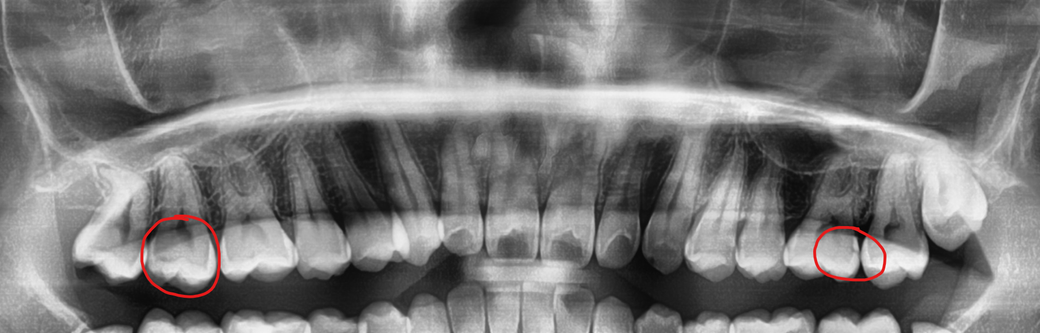

아래 사진 빨강 동그라미 두곳 레진치료 해야한다는디 맞나요..? 한쪽은 옆면에 구멍이 뚫려있다하구 한쪽은 잘 모르겠는데.. 레진 치료 해야하나요?

치아 사이에 충치가 있어 보이네요. 치아 상태에 따라서 레진을 할수도 있고 인레이를 해야될수도 있습니다.

레진이나 인레이 치료를 필요로 해 보입니다. 충치가 있는 것은 사진상에 보이고 있습니다.